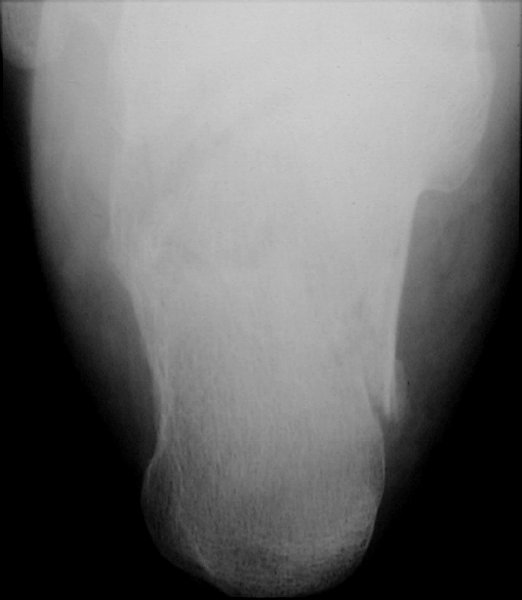

Return to Calcaneus Fracture